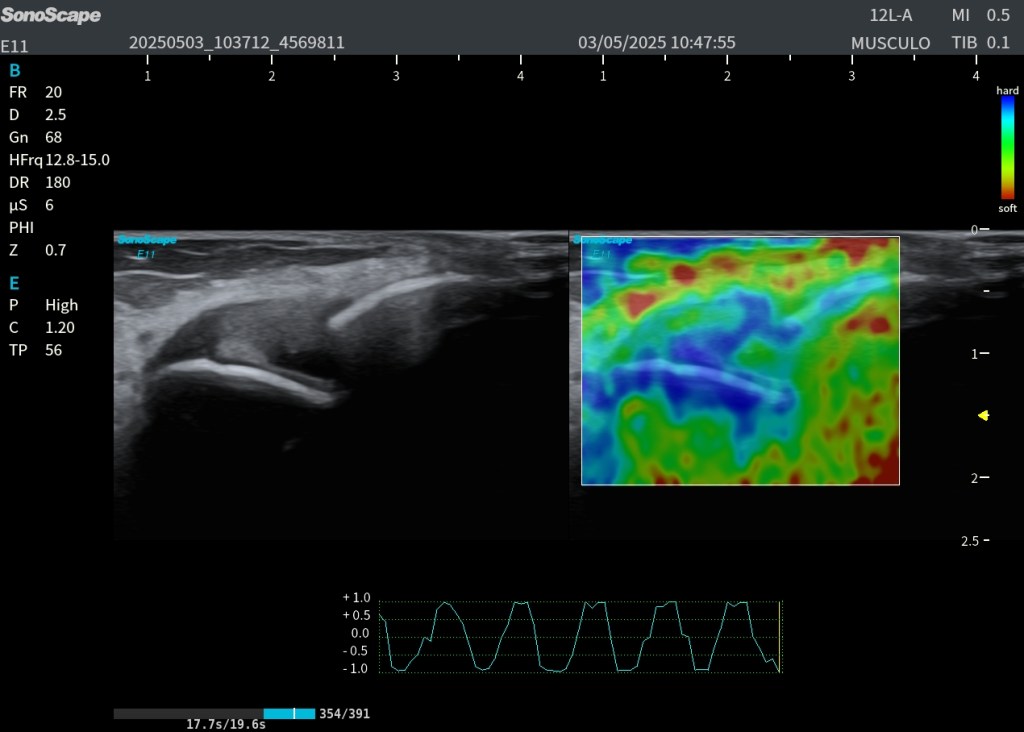

El estudio ecográfico longitudinal y transversal del compartimento posterior superficial muestra:

- Rotura de la aponeurosis del gastrocnemio medial (GA) con afectación extensa de la aponeurosis libre (FGA).

- Presencia de hematoma intermuscular parcialmente organizado, con septos internos bien definidos que indican fase no aguda del proceso.

- Retracción parcial del vientre muscular del gastrocnemio medial.

- Asincronía visible entre gastrocnemio y sóleo durante maniobras dinámicas de dorsiflexión y plantiflexión.

- En la imagen de elastografía de strain, se evidencia menor rigidez en la zona del hematoma, como es esperable, y mayor rigidez en las fibras retraídas, que se comportan de forma más fibrosa y densa en la fase de cicatrización.